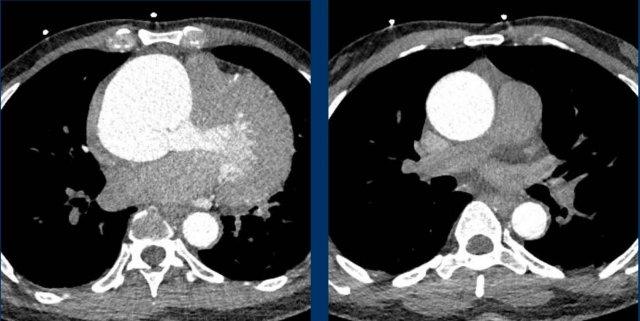

Giãn buồng tim phải

Nhĩ phải thường giãn do bệnh lý van ba lá, có thể là nguyên phát hoặc thứ phát do bệnh lý thất phải. Thất phải có thể bị giãn vì nhiều nguyên nhân khác nhau, trong bối cảnh cấp tính hoặc mạn tính hơn.

Trong bối cảnh cấp tính, thuyên tắc huyết khối ồ ạt có thể dẫn đến tắc nghẽn đường ra và phồng giãn thất phải, tình trạng này có mối tương quan nghịch với tỷ lệ bệnh tật và tử vong.

Trong bối cảnh mạn tính hơn, giãn thất phải có thể gặp trong bệnh cơ tim phải, các bất thường bẩm sinh và tăng áp động mạch phổi do nhiều căn nguyên khác nhau, bao gồm cả bệnh huyết khối tắc mạch mạn tính.

Quá trình thích nghi và tái cấu trúc của thất phải biểu hiện theo một phổ liên tục gồm giãn, phì đại và cuối cùng là suy chức năng.

Suy tim phải sẽ dẫn đến cổ trướng và phù toàn thân, trái ngược với suy tim trái gây ứ huyết với phù phổi và tràn dịch màng phổi.

Hình ảnh

Huyết khối bám thành trung tâm ở bệnh nhân bị bệnh huyết khối tắc mạch mạn tính kèm giãn buồng tim phải, phù hợp với tăng áp động mạch phổi do huyết khối tắc mạch mạn tính (CTEPH).